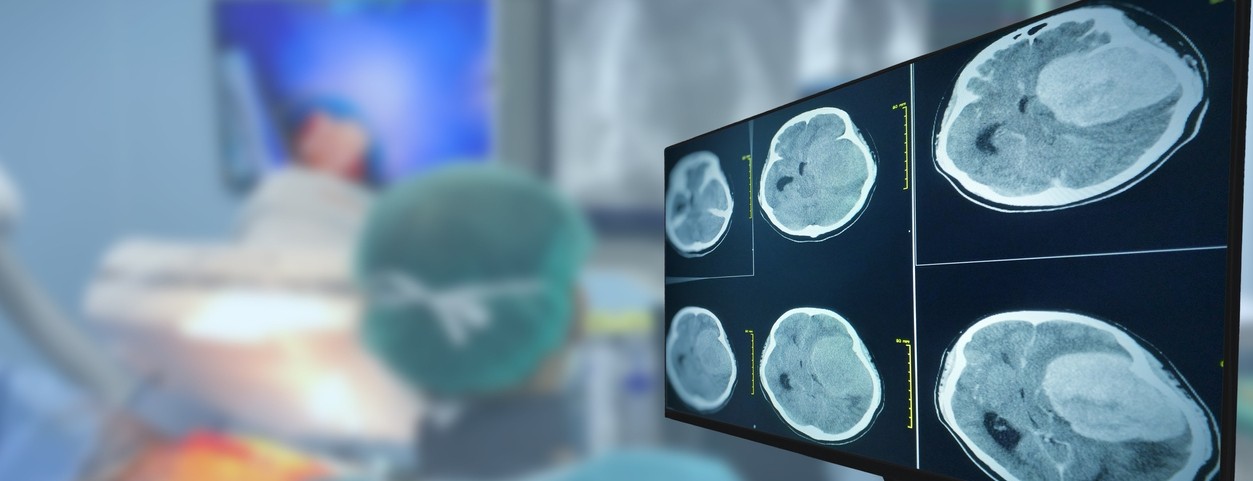

New research out of the University of Cincinnati shows a targeted drug therapy had positive results in delaying the progression of a specific form of glioma, which is a slow-growing brain tumor.

Researchers studied 331 people with this disease and compared the study drug to a placebo. Those given the targeted therapy did not have disease progression for more than 27.7 months. For those in the placebo group, it was only 11.1 months.